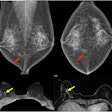

International team pinpoints causes of missed breast cancers